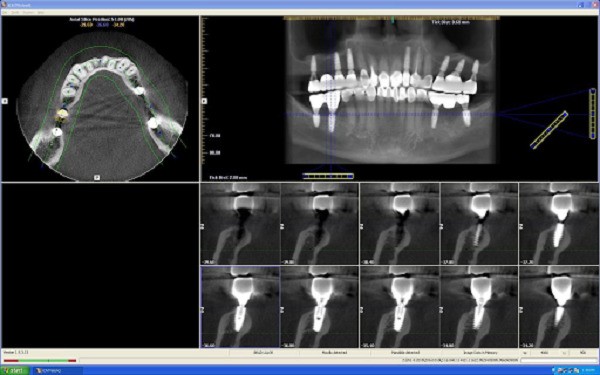

Chụp cắt lớp vi tính CT Cone Beam (3D)

Chụp cắt lớp vi tính Cone Beam 3D là công nghệ cao cấp nhất hiện nay trong chẩn đoán răng miệng, cung cấp hình ảnh không gian 3 chiều chính xác nhất. Loại hình này phù hợp trong các ca phẫu thuật Implant, chỉnh hình và các vấn đề phức tạp khác liên quan đến cấu trúc xương mặt và hàm.

Chi phí của chụp CT Cone Beam dao động trong khoảng 2.500.000 – 4.500.000 đồng, tùy theo trung tâm và công nghệ sử dụng. Tuy giá thành cao hơn nhiều so với các dạng khác, nhưng ưu điểm của nó là chính xác, rõ nét đến từng chi tiết nhỏ nhất, giúp các bác sĩ quyết định phương án điều trị tối ưu, giảm thiểu rủi ro và tăng tỷ lệ thành công.